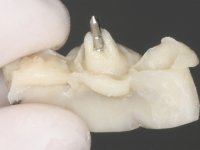

Endodontic treatments were performed and a metalic non screwed intra radicular post was placed on tooth 1.1. An alginate impression was made for laboratory confection of a reinforced acrylic provisional bridge, with teeth 1.1 and 2.2 as abutments and 2.2 as a pontic. After preparation of tooth 1.1 and root preparation of 2.1, the bridge was relined in mouth with self-polymerizable acrylic using a metal post for further retaining the prepared root canal on 2.1. Tooth 2.2 was cut at the gingival level to function as support. In the same session, the impression of the root canal of the 2.1 was made for the laboratory confection of a cast post and core. A double mixture technique with plastic tutor was used after previous canal vaseline with endodontic file and cotton. The provisional bridge was provisionally cemented and the cast post and core was made in the laboratory. Cast post and core cementation was made with resin-reinforced glass ionomer cement and the provisional bridge had to be readjusted to the new situation by removing the post at the site of 2.1. After careful surgical planning, a dental implant was placed, simultaneously with extraction of the root of tooth 2.2. The provisional bridge was placed by resting on the healing screw placed in the implant. The respected osteointegration period was 12 weeks, during which the provisional bridge was relined twice. After complete maturation of hard and soft tissues, definitive impressions were made. The gingival retraction technique was applied with an impregnated retraction cord and impression was performed using double mixture, open tray impression technique. A custom precious metal abutment implant was prepared in the lab, along with 3 metal caps to be used as infrastructures for the metal ceramic crowns. Particular care was taken in the confection of the cervical finishing line of the implant abutment, in order to follow the soft tissues emergence profile. Proof of infrastructures was done in the mouth being evaluated clinically and imagiologically. Collection of color information was done by the ceramist at the office. Ceramic was applied in the laboratory and the finished work was placed in the mouth after approval by the patient. Definitive cementation was made with resin-reinforced glass ionomer cement, and the first crown to be cemented was that of the implant, to facilitate removal of the excess.